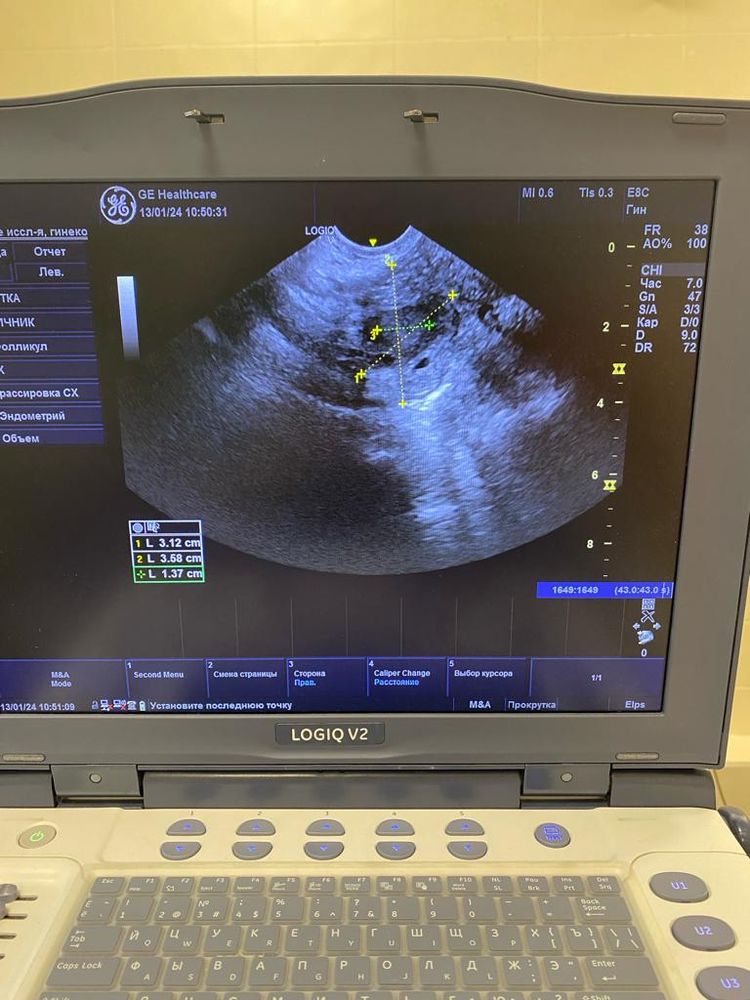

Юлия , Изображение Изображение Изображение Изображение Изображение

Ольга, по этим снимкам овуляция не вот вот. А до нее еще как минимум неделя от этого УЗИ. Фолликулы до 10 мм. И нет доминанта

Ольга, не нужны снимки, нужен протокол УзИ. Описание яичников, срез, ДФ, эндометрий. Врач узи в нескольких проекция смотрит. Я как врач, на этих снимках не вижу ДФ, фолликулы до 10 мм.. Поэтому вообще-то говорить что была овуляция сложно. Сейчас делать УЗИ нет смысла. Ждите менструацию, она начнется со дня на день. Делайте УЗи уже в след цикле в динамике, по мере роста ДФ и подтверждайте овуляцию через 7 дней после ее наступления и берите протоколы УЗИ. Сейчас мы с Вами просто гадаем на кофейной гуще.